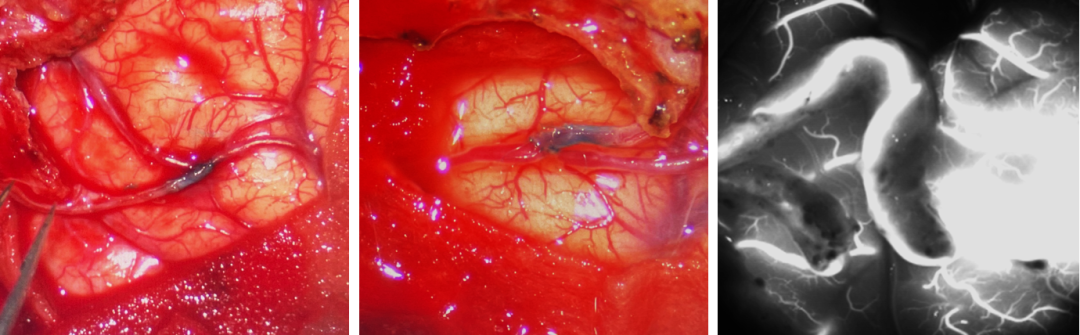

今天为大家分享的是,由复旦大学附属华山医院顾宇翔教授和倪伟医师带来的:巨大复杂颈内动脉分叉部动脉瘤一例,欢迎阅读、分享。

术前诊断: